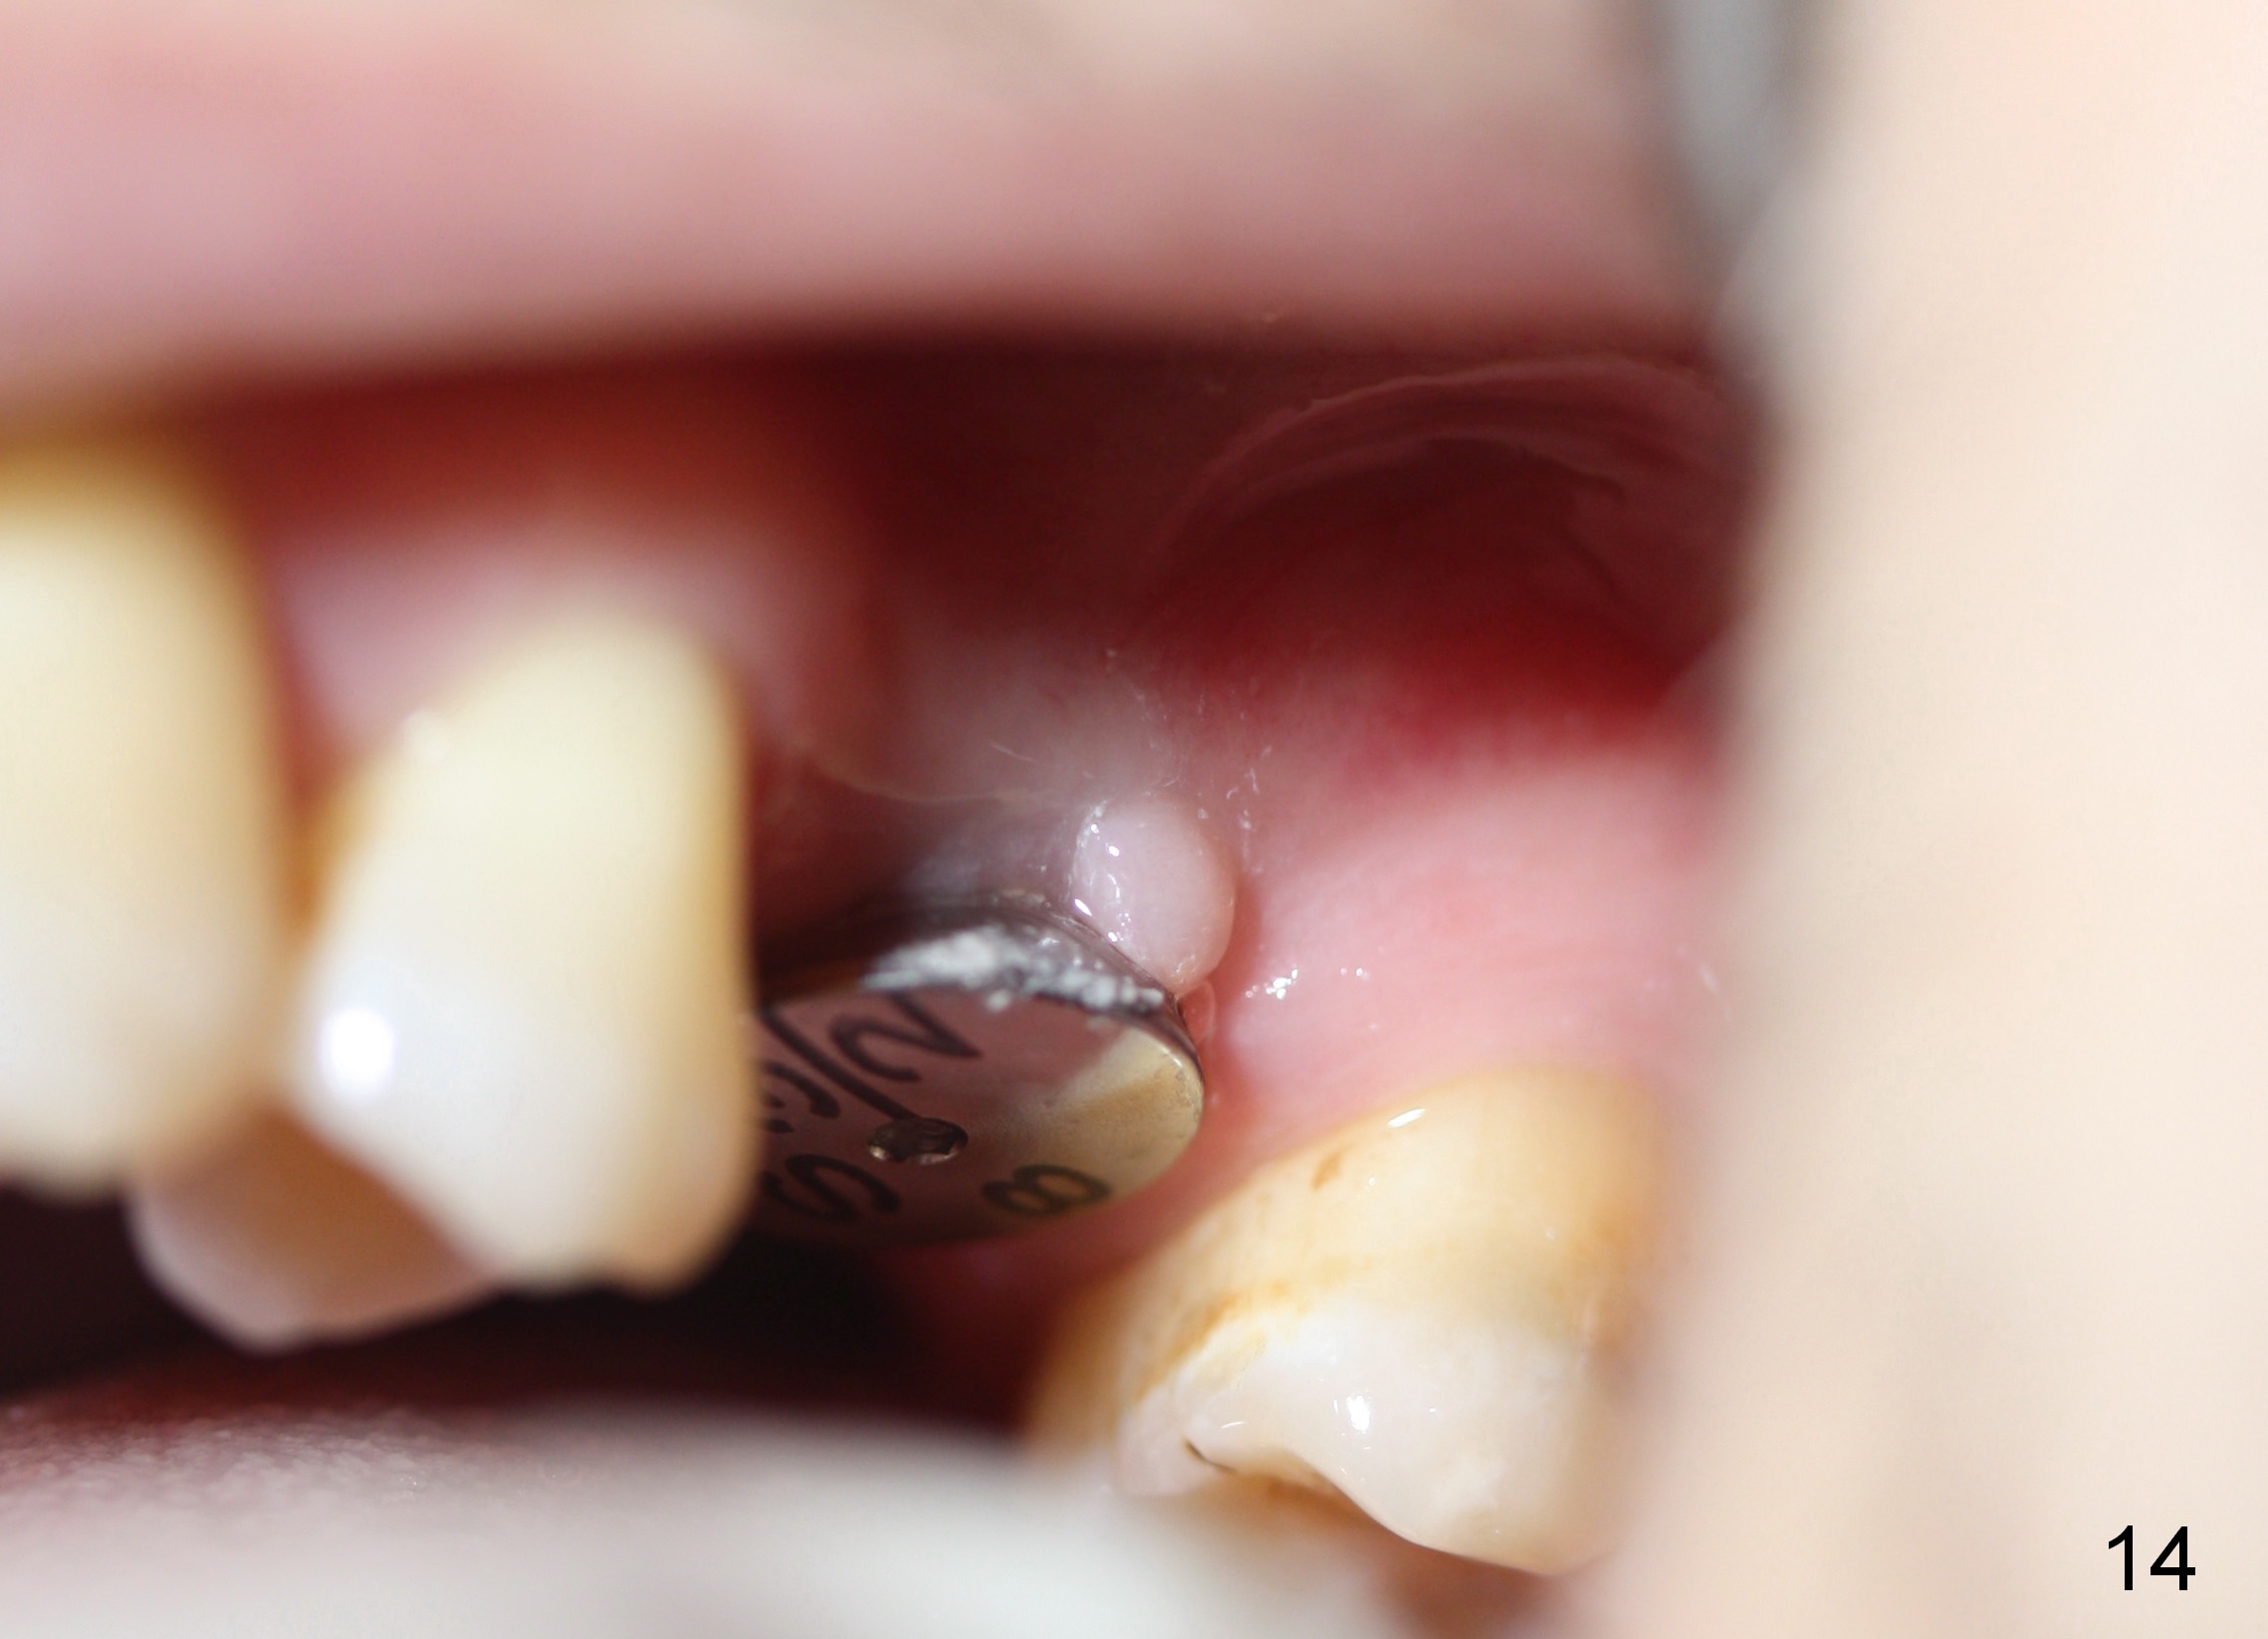

A 45-year-old man has lost the tooth #14 for a while (Fig.1); bone height is 5.4 mm. An extra wide and short implant is planned. Torus palatinus is large, suggesting that bone density should be high. A 6 mm tissue punch is chosen, but it is placed more palatal. If it were placed in the middle of the ridge, there would be no buccal keratinized gingiva (incision may avoid this issue). Additionally, the buccal portion of punch is made incomplete so that there is pedicle on the buccal side when the flap is raised (Fig.4,8: F). It is expected that the excess portion of keratinized tissue will form thick gingiva buccally. Osteotomy proves that bone is dense (Fig.2 (4.5x11 mm tap). Typical sinus lift is finished with placement of 6.4x6 mm (extra wide) bone-level implant (Fig.3, >55 Ncm). Following further torque, Fig.4 shows that the implant (I) is sub-gingival (<). Bitewings are taken to confirm that the implant plateau is at the crestal level (Fig.5,6 ^). PA shows sinus lift (Fig.7 *). The lingual aspect of the implant and healing abutment (H) is further bone grafted and covered by collagen dressing (Fig.8 *). The wound is protected with perio dressing. When the latter dislodges 7 days postop, the collagen dressing and bone graft are lost as well (Fig.10), while the buccal flap remains vital (Fig.9). The lingual exposed plateau should be able to heal normal. The collagen dressing should have been fixed in place by suture or as simple as a dental floss. There is mild nasal hemorrhage 1-2 days postop, possibly related to sinus membrane perforation and inability of Collagen Dressing to cover the perforation and contain the bone graft. When the patient returns for #9 implant placement in 3 weeks postop, the buccal flap reduces in size (Fig.11 *), while the palatal wound has healed with minimal exposure of the implant (Fig.12). Sinus graft remains in place 3 months postop (Fig.13); the buccal flap appears to have incorporated into a part of the gingiva (Fig.14). The bone density of the sinus lift appears to increase 10 days later when an abutment is placed (Fig.15 *). Although oral hygiene is pristine, there is apparent crestal bone resorption 12 months (Fig.16) and 20 months (Fig.17) post cementation, probably due to unfavorable crown/implant ratio and bruxism as well as pre-implantation bone loss (Fig.18,19). In contrast, an immediate implant in the same patient avoids pre- or post-implantation bone loss. In fact both the soft (Fig.20) and hard (Fig.21) tissues remain healthy 2 years 8 months post cementation. The sinus lift remains 3 years 8 months post cementation (Fig.22), while the crestal bone loss persists. The patients keeps complains of food impaction distal associated with bad smell 4 years 1 month post cementation. In fact the distal proximal contact is within normal limit. The bad smell is probably due to crestal bone loss (Fig.23 (pan), 24 (CT) *) and periimplantitis. Bone graft, PRF and Cytoplast membrane will be needed and fixed in place with long healing screw. When the patient returns for crown redo, he also reveals floss related gingival hemorrhage. There is pain associated with palatal sulcus probing with light gingiva erythema. Review of CT coronal section shows possible palatal (Fig.25 P) bone loss (*).